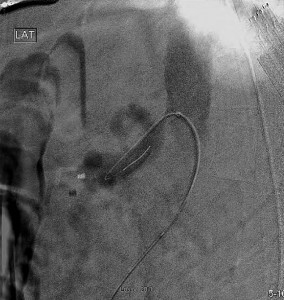

Following treatment of restenosis, there was rapid flow of contrast into the splenic and common hepatic arteries (Fig 3).

Mesenteric artery intervention

Selective injection of the celiac artery showing a patent proximal stent post-angioplasty. The wire tip is visible in the splenic artery in this lateral projection.